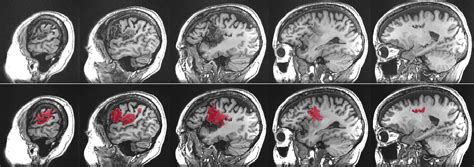

Let’s talk about causes of aphasia . Understanding what triggers this language disorder is super important for prevention and treatment strategies. The primary cause of aphasia is damage to the language-dominant areas of the brain. For most people, the left hemisphere of the brain is responsible for language functions. When these areas are injured, aphasia can result. The most common culprit, as we’ve touched upon, is a stroke . Strokes occur when blood supply to a part of the brain is interrupted, either by a blockage (ischemic stroke) or by bleeding (hemorrhagic stroke). This lack of blood flow deprives brain cells of oxygen, causing them to die. Depending on which part of the brain is affected, language abilities can be severely impacted. Another significant cause is Traumatic Brain Injury (TBI) . TBIs can happen from blows to the head, falls, or accidents. The widespread nature of the damage in a TBI can affect various brain functions, including language. Brain tumors can also lead to aphasia . Whether the tumor is malignant or benign, its growth can press on or invade brain tissue, disrupting normal function, including language processing. Brain infections , such as encephalitis (inflammation of the brain), can also cause damage to language areas. Lastly, neurodegenerative diseases are a cause, particularly Primary Progressive Aphasia (PPA). PPA is a group of brain disorders caused by specific types of dementia that target the brain’s language networks. Unlike other causes where aphasia might appear suddenly, PPA is typically a gradual decline. Each of these causes of aphasia presents unique challenges in terms of diagnosis, treatment, and prognosis. Knowing the cause helps medical professionals tailor the approach to managing aphasia , aiming to restore as much language function as possible and improve the quality of life for those affected. It’s a complex puzzle, and identifying the root cause is a critical piece.

Types of Aphasia

Now, let’s get into the nitty-gritty: the types of aphasia . Because aphasia is caused by damage to different parts of the brain, it doesn’t just show up as one single problem. Instead, it’s classified into various types, each with its own set of characteristics. This classification helps speech-language pathologists (SLPs) understand the specific challenges a person is facing and develop targeted therapy. The two main categories are often fluent aphasia and non-fluent aphasia , with further subtypes within each.